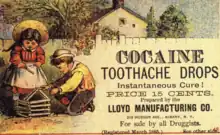

There are many causes of toothache and its diagnosis is a specialist topic, meaning that attendance at a dentist is usually required. Since many cases of toothache are inflammatory in nature, over the counter non-steroidal anti-inflammatory drugs (NSAIDs) may help (unless contraindicated, such as with a peptic ulcer). Generally, NSAIDs are as effective as aspirin alone or in combination with codeine.[10]: 41–43 However, simple analgesics may have little effect on some causes of toothache, and the severe pain can drive individuals to exceed the maximum dose. For example, when acetaminophen (paracetamol) is taken for toothache, an accidental overdose is more likely to occur when compared to people who are taking acetaminophen for other reasons.[46] Another risk in persons with toothache is a painful chemical burn of the oral mucosa caused by holding a caustic substance such as aspirin tablets and toothache remedies containing eugenol (such as clove oil) against the gum.[14] Although the logic of placing a tablet against the painful tooth is understandable, an aspirin tablet needs to be swallowed to have any pain-killing effect. Caustic toothache remedies require careful application to the tooth only, without coming into excessive contact with the soft tissues of the mouth.